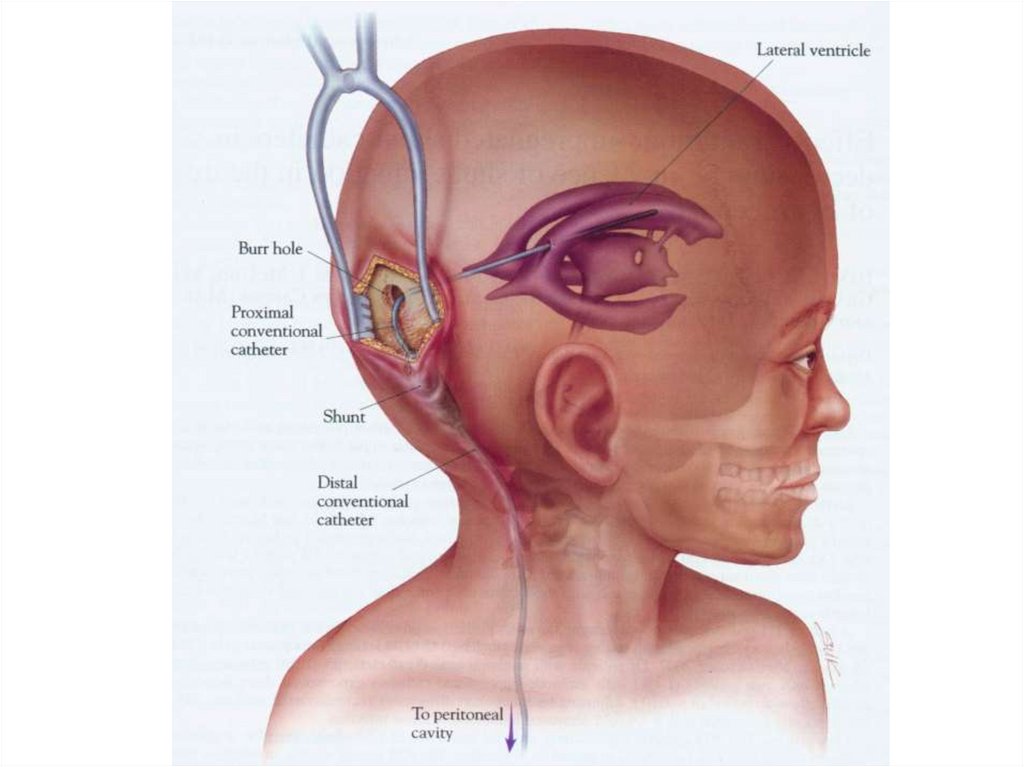

Вентрикуло-перитонеальный шунт: Показания и применение

Раздел: Фотоальбом решений